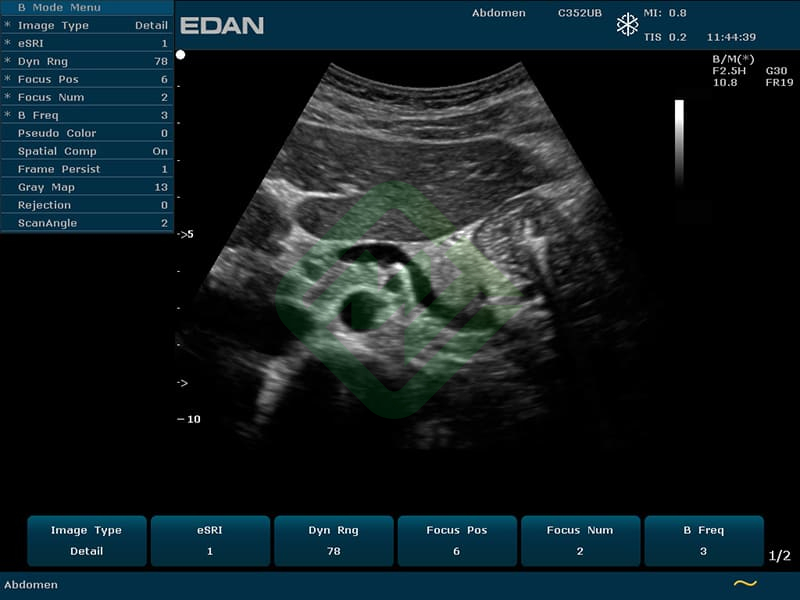

- Режимы сканирования: B, M, CDI, PW, CW, PDI, DPDI или B, M, ЦДК

- Портативный аппарат УЗИ Edan U50 (со стандартным комплектом для кардиологии) представляет собой современную портативную ультразвуковую систему высокого уровня, обеспечивает превосходное качество изображения и позволяет получить больше информации в разных видах исследований с помощью расширенного режима работы

- Предназначен для гинекологических, акушерских, педиатрических, урологических, трансвагинальных и кардиологических исследований, а также исследований брюшной полости, поверхностных органов, периферических сосудов и опорно-двигательного аппарата

— конвексным C352UB: частотный диапазон датчика 2–6 МГц, угол обзора 70°, глубина сканирования 320 мм, количество элементов 128

- Датчик конвексный ультразвуковой C352UB — 1 шт.